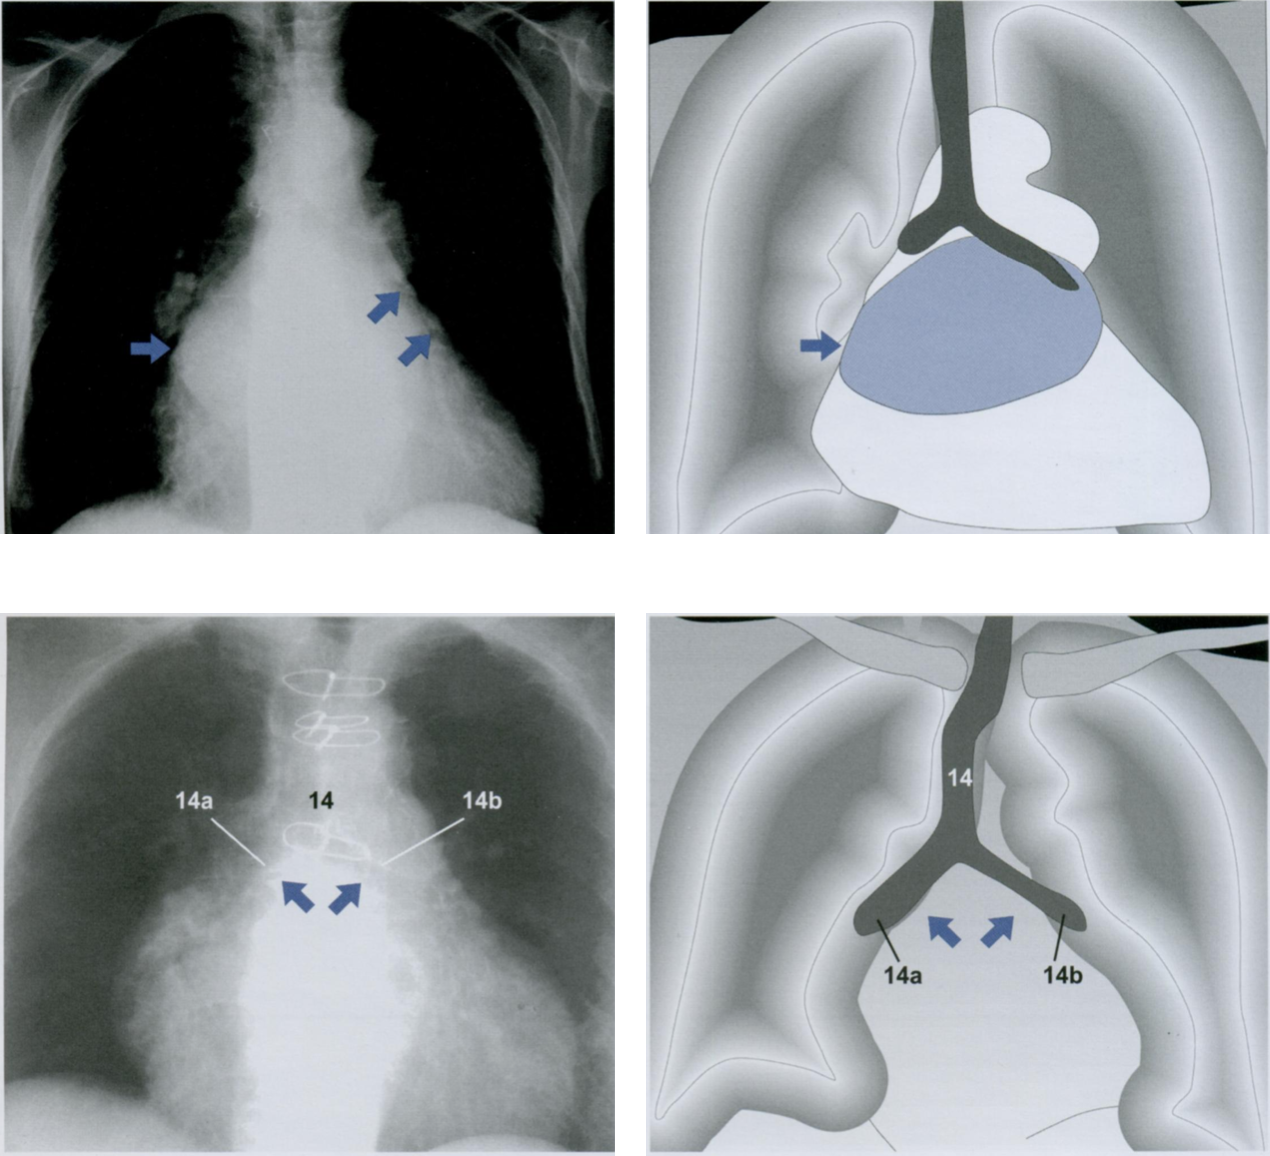

Оцените Rx снимки.

Назовите рентген-признаки патологий аортального клапана.

Патология аортального клапана часто формирует аортальную конфигурацию сердца на рентгенограмме грудной клетки (первый и второй снимки).

Основной механизм возникновения тот же, что и при патологии митрального клапана. Стеноз или недостаточность аортального клапана приводят к гипертрофии или дилатации левого желудочка. В результате край левого желудочка (косая стрелка вверх) смещается влево при сохранении талии сердца (косая стрелка вниз).

«Бычье сердце» (третий снимок) - термин, обозначающий крайнюю степень увеличения тени сердца в обе стороны с СГИ более 0,66. Возможными причинами являются тяжелая степень аортальной недостаточности, кардиомиопатия и сочетанные пороки сердца.

В отличие от равномерного увеличения сердечной тени при дилатации его камер (третий снимок), аневризма желудочка проявляется округлым выпячиванием (стрелка на четвертом снимке) на контуре тени сердца (четвертый снимок). В сомнительных случаях диагноз устанавливается при эхокардиографии, когда определяется парадоксальное сокращение (дискинезия) стенки левого желудочка в области аневризмы.